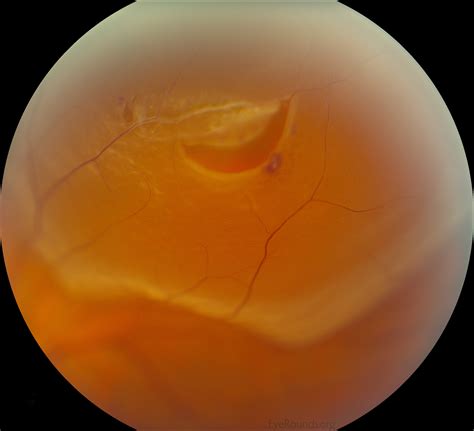

A retinal tear is a serious medical event that occurs when the vitreous gel—the clear substance that fills the eye—pulls away from the retina, causing a rip or a hole. Because the retina is the light-sensitive tissue at the back of the eye, any structural damage requires immediate attention to prevent vision loss. When patients receive a diagnosis, their first and most urgent question often revolves around the retinal tear prognosis. Understanding the outlook after this diagnosis is crucial for managing expectations, preparing for potential procedures, and recognizing the symptoms that necessitate emergency care. Fortunately, with prompt intervention, the prognosis for most individuals is excellent, though it depends heavily on the timing of treatment and the specific location of the tear.

Upon visiting an ophthalmologist or retina specialist, the doctor will dilate your pupils to get a clear view of the entire retinal surface. They use specialized lenses to examine the peripheral retina where tears are most likely to occur. If a tear is detected, the specialist will determine whether it requires immediate stabilization. The retinal tear prognosis is significantly better if the tear is caught before it progresses to a full retinal detachment—a condition where the retina completely peels away from the wall of the eye.

Once a tear is identified, treatment is generally non-invasive compared to surgery for detachment. The goal of treatment is to “weld” the retina back to the underlying tissue to prevent fluid from seeping behind it. The most common procedures include: